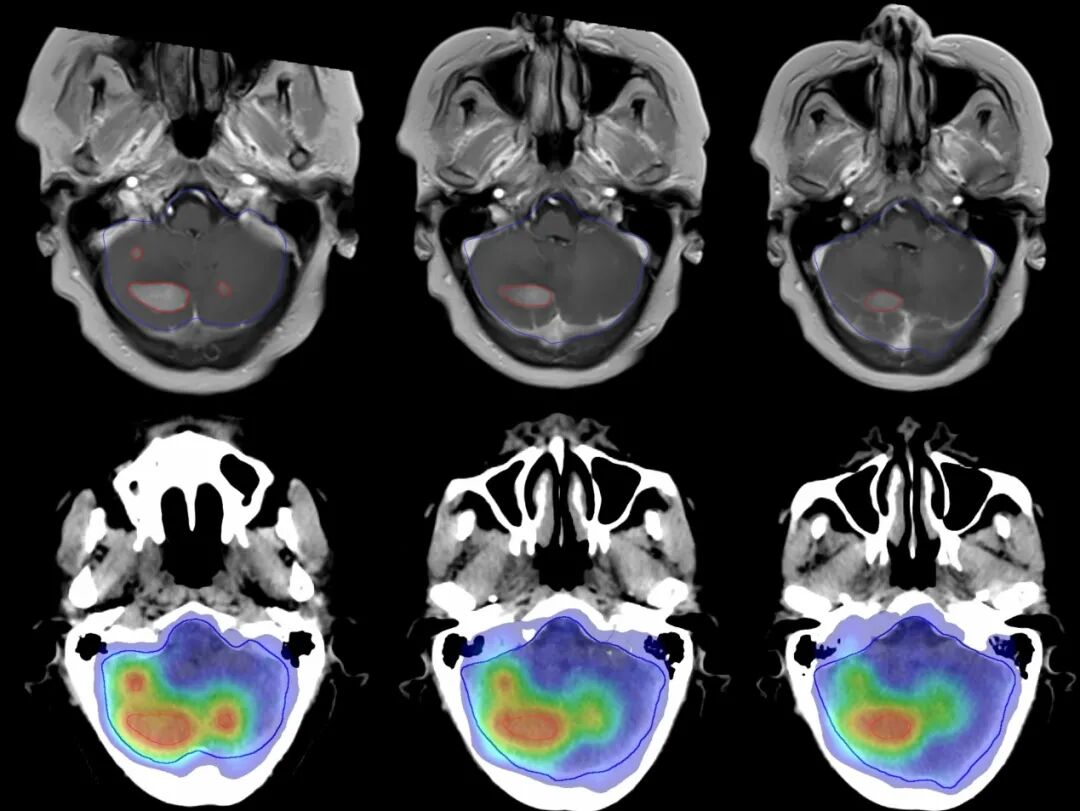

【學科風采】乳腺癌患者千里求醫(yī),成功治療多發(fā)腦轉移瘤、脊髓轉移、腦膜轉移、椎管內多發(fā)轉移結節(jié)、肺炎及肺門轉移患者